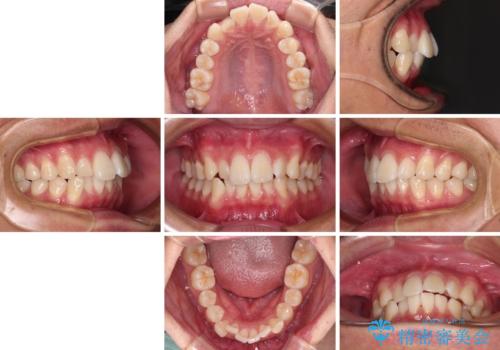

前歯のデコボコをインビザラインで綺麗に改善

- 上下前歯のデコボコとクロスバイトを気にして来院された患者様です。

インビザラインを用い、IPR(歯と歯の間を削る)と歯列全体を拡大させることで、歯並びを整えていくこととしました。

毎日22時間の装着時間を徹底してくださったのですが、左右ともに臼歯が咬合しなくなるという、インビザライン独特の症状が強く長く続いてしまい、終了するまでに長期間を要してしまいました。